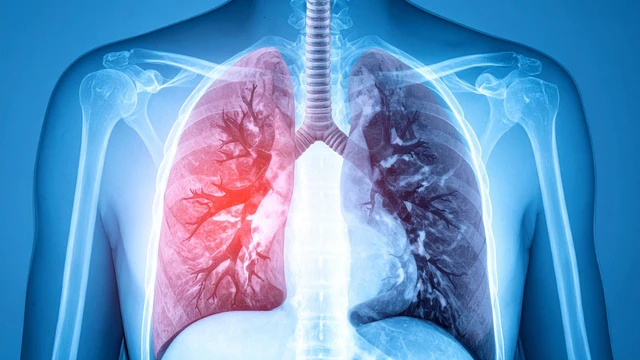

Giãn động mạch phổi là một tình trạng y khoa nghiêm trọng, có thể là dấu hiệu cảnh báo của nhiều bệnh lý tim mạch và hô hấp tiềm ẩn. Vậy giãn động mạch phổi có thực sự nguy hiểm hay không và những phương pháp chẩn đoán, điều trị hiện đại nào đang được áp dụng để quản lý hiệu quả tình trạng này?